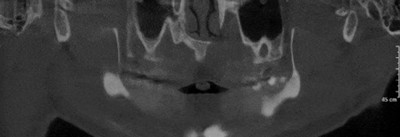

上颌窦底,骨小梁与下颌神经管清晰可见

植体周围无阴影,植体螺纹清晰可见